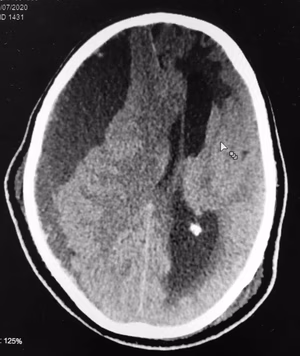

O papel do Neurocirurgião na estenose de carótida e AVC.